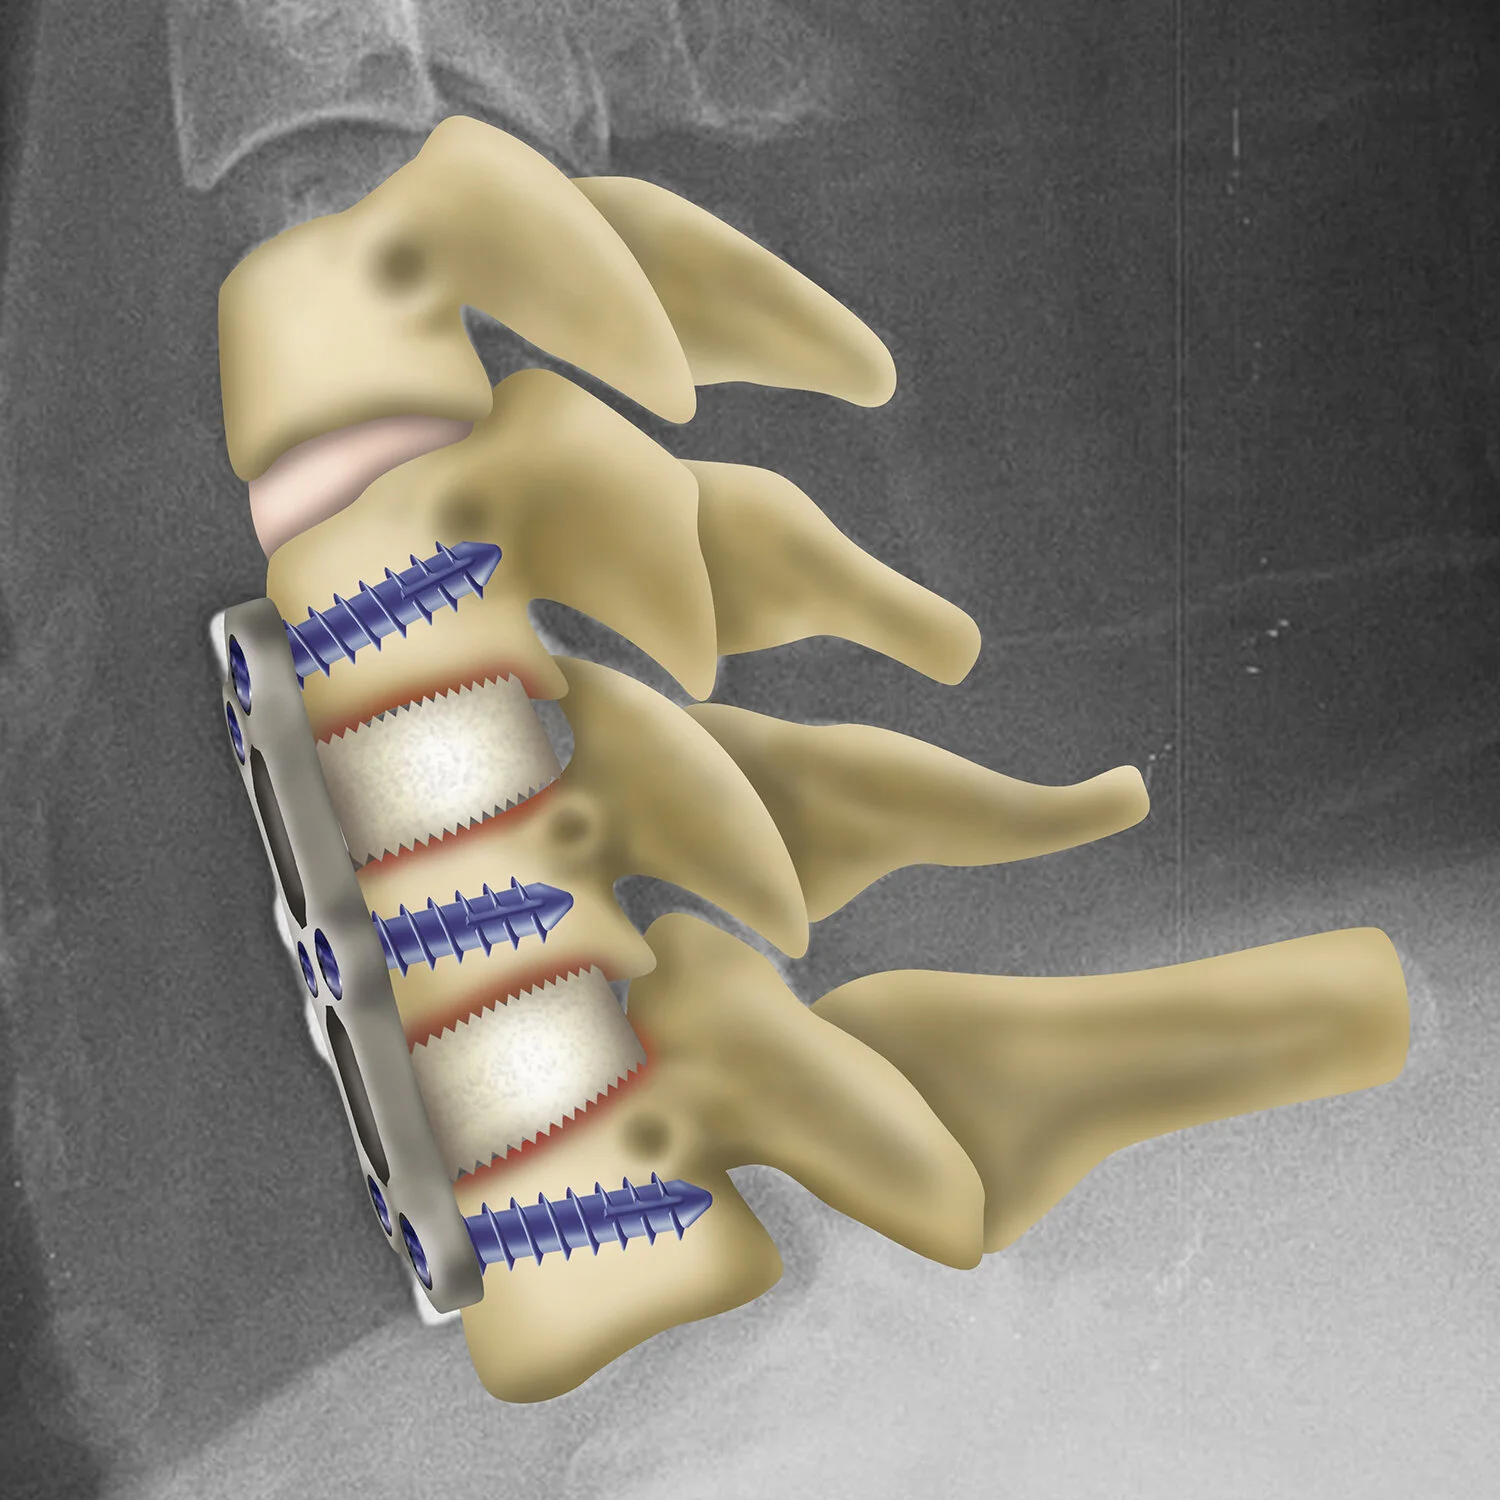

![Anterior cervical plate installation]()

Anterior cervical plate installation